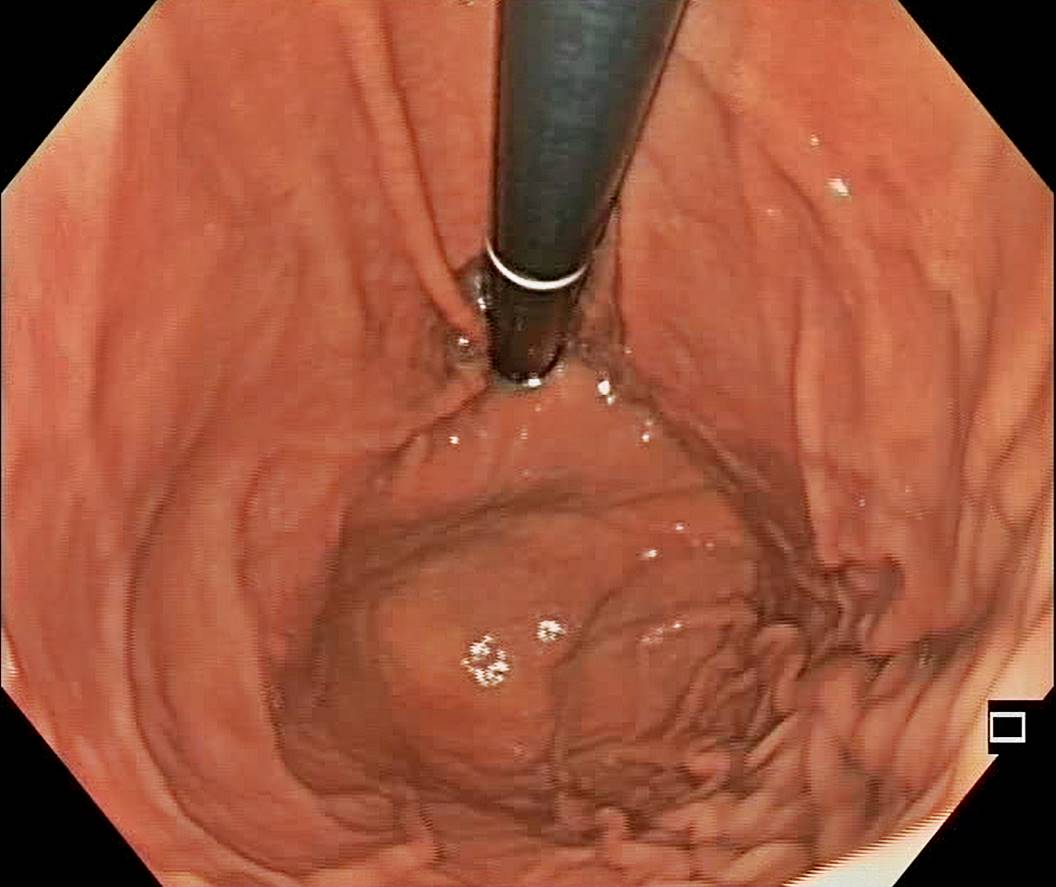

A Normal Gastric Fundus

A normal gastric fundus. Just click on a picture!

Diverticulum in the gastric fundus